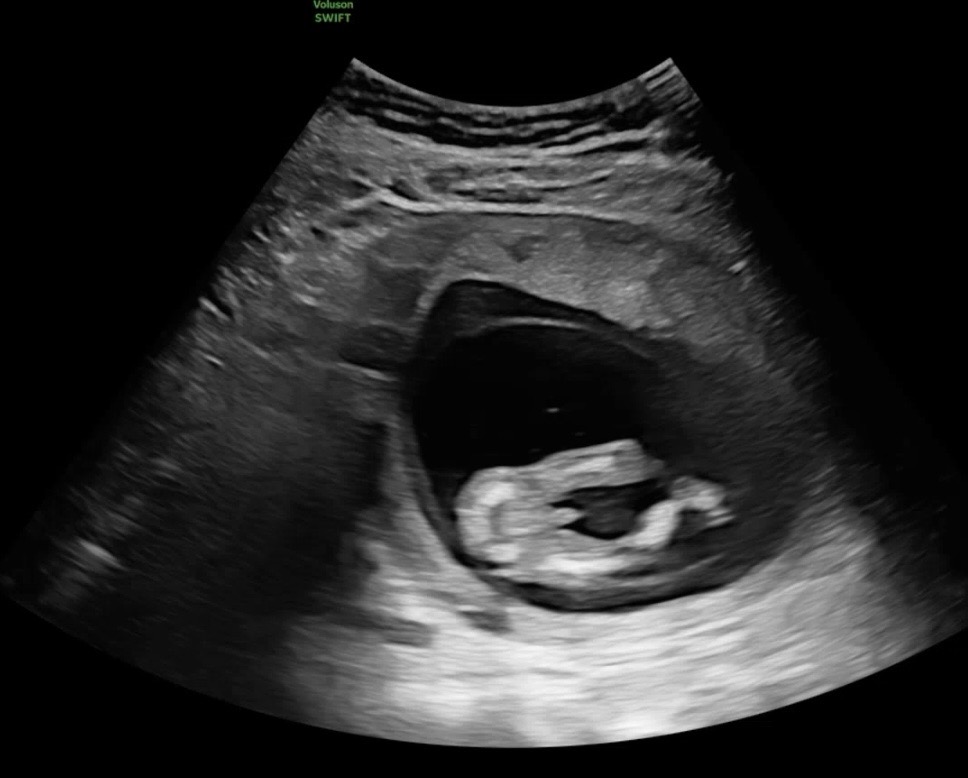

답글이 너무 많이 달려서 놀랐어요!! 너무 많아서 답글은 모두 달지 못했지만! 하나하나 다 읽어보았어요😌🩷 아쉬운 마음이 정말 많이 가셨어요!! 물론 내 자식이니 당연히 사랑으로 감싸줘야죠♡♡ 저도 이 집안의 유일한 공주가 되어보렵니다♥️♥️♥️♥️ 모두 감사해요ʕ”̮ॽु⋆⁺₊⋆ ♥️ ----------------------------------------------------- 딸을 너무도 원했던 오늘로 15주차 맘입니당ㅎㅎ 젠더리빌 하려고 설레는 맘으로 니프티 검사 결과지 찾으러 갔다가 초음파를 봤는데... 네... 결과지는 필요 없었어요.......ㅎㅎ(14주차 1일이라 안 보일 줄 알았음 ㅠㅠ) 뱃속 아가한테 미안하게 아쉬운 마음이 가시질 않네용.. 병원 나오는 길부터 지나가는 아이들이 어쩜 하나같이 다 딸인지...ㅋㅋㅋㅋㅋㅋ 너무 부러웠어용ㅎㅎ...